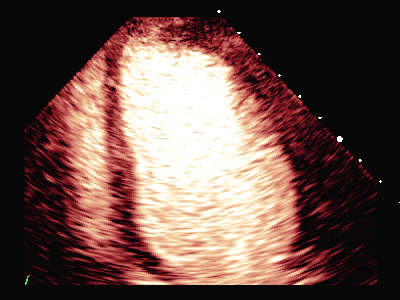

图(6)

图(7)

DSA:前降支(LAD):近段可见85%狭窄,血流TIMI 3级。PCI:于狭窄段置入支架1枚。